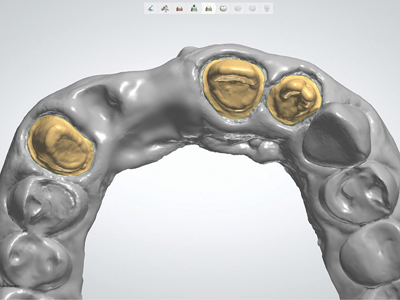

Fig. 11

Pre-operative condition #16.

Fig. 12

Core and preparation #16, DO resin #15.

Fig. 13

Virtual model ready for CAD design. CAD designed restoration.

Monolithic translucent zirconia crown #16

- 61-year-old female.

- Cc: Cracked tooth #16

- Patient with high esthetic demand

- Moderate force factors